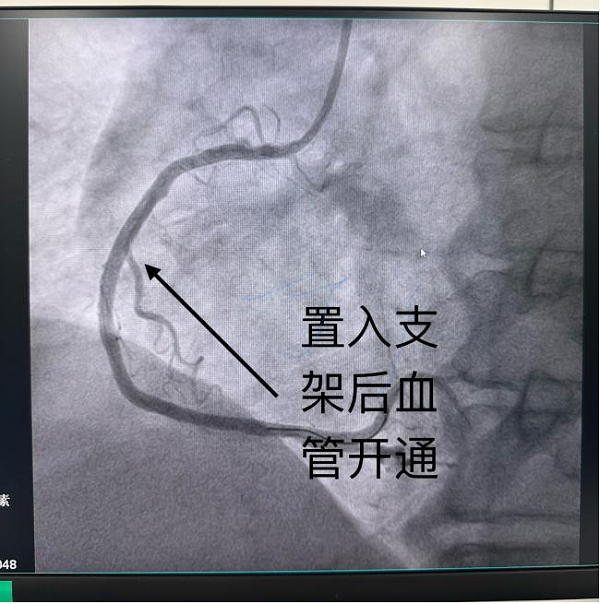

11:14,患者到达兰陵县人民医院胸痛中心,绿色通道直接将患者送入介入手术导管室进行急诊冠脉造影检查。此时县人民医院急诊介入团队已在介入导管室做好充分术前准备等待患者到来。冠脉造影检查发现患者的右冠状动脉完全闭塞,立即行介入治疗。11:31,导丝通过病变狭窄处,并于病变处植入支架1枚,从进入院区至血管开通仅仅用时17分钟,手术顺利结束。术后患者转入心内科病房进一步稳定病情,监测生命体征变化。